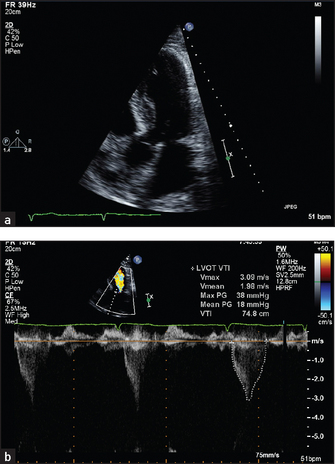

• In continuous and pulsed wave Doppler, interrogation of the returning ultrasound signal enables calculation of the Doppler shift caused by reflection of the beam from moving columns of blood. This means that the velocity and direction of blood flow from different parts of the heart can be measured. The Doppler signal can be displayed as a velocity wave. By superimposing the Doppler callipers on the two-dimensional image, the echocardiographer is able to measure the velocity of jets of blood from a particular area (e.g. in the ascending aorta just beyond the aortic valve cusps; see Figure 8.17).

Figure 8.17 (a) Four-chamber view of a patient with prolapse of both mitral valve leaflets. This systolic frame shows the closed mitral leaflets (anterior on the left) bowing back into the left atrium as they face the full force of left ventricular systole. (b) Four-chamber view of a 50-year-old woman with a middle and late systolic murmur. A brightly coloured (high-velocity) jet is seen in this systolic frame, extending from the centre of the mitral valve well back into the left atrium. (From Baker T, Nikoli

G, O’Connor S, Practical cardiology, 2nd edn. © 2008, Sydney: Elsevier Australia.)

Sector scanning and M mode pictures can provide information about valve morphology, for example thickening or prolapse of the leaflets (see Figure 8.17). Doppler echo can reveal abnormal jets of blood, for example regurgitant jets, and measure flow velocity across valves. This measurement can be used to estimate the valve gradient (the difference in pressure across the valve).

3. Mitral regurgitation and mitral valve prolapse. Here the mitral valve may appear abnormal and abnormal coaptation of the leaflets may be visible (see Figure 8.17).

4. Aortic stenosis. Thickening and calcification (bright echoes) of the aortic valve are usually visible (see Figure 8.19). The movement of the valve cusps may appear reduced. The anatomy of the valve may be apparent. Doppler interrogation of the jet of blood in the ascending aorta will enable its velocity to be measured. A simple formula enables estimation of the pressure gradient to be made from this measurement.